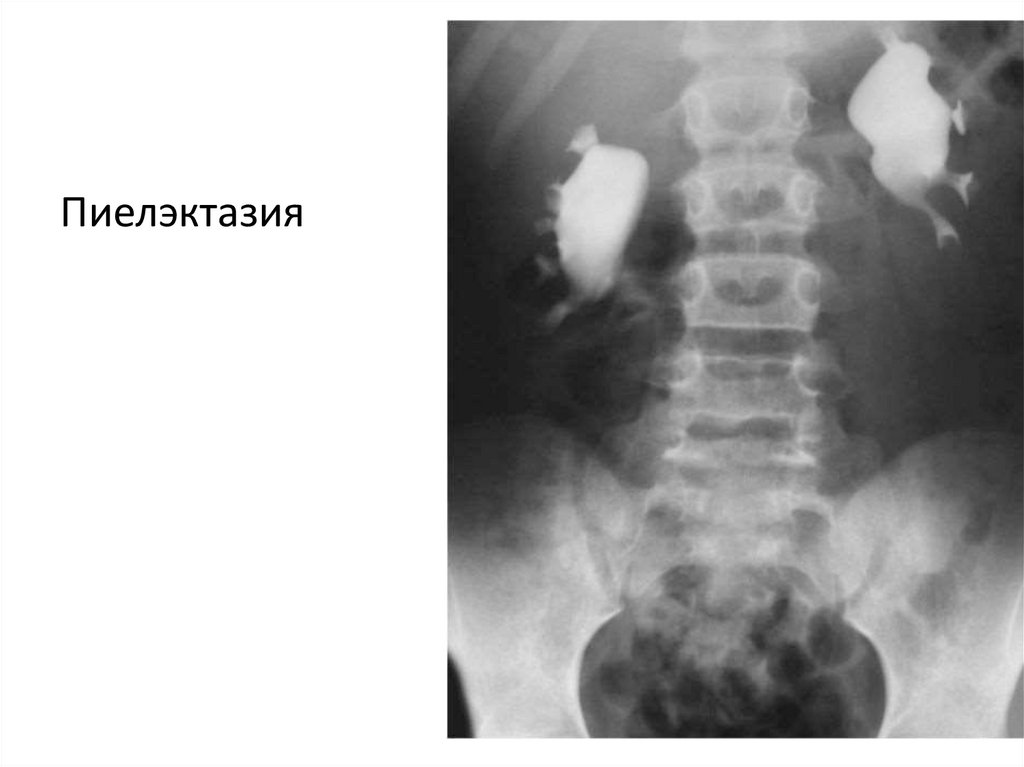

Пиелэктазия

17.